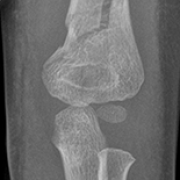

Closed Reduction Percutaneous Intramedullary Fixation with Kirschner Wires in 4 Children with Displaced Fractures of the Distal Humerus

Rufa Wang, Pengfei Zheng

DOI: 10.12659/MSM.935448

Med Sci Monit 2022; 28:e935448